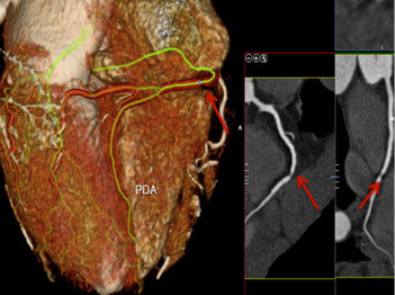

CT Coronary Angiography is an advanced CT scan of the heart arteries. It helps doctors visualise blood flow, identify narrowing or blockages, and assess overall coronary artery health.

Calcium score CT coronary angiography is an additional measurement that estimates calcium deposits in heart arteries — helping assess future heart risk even before blockages develop.

At Trinity Hospital and Heart Foundation, CT Coronary Angiography is used as a gatekeeper investigation — providing detailed artery mapping for precise clinical decisions.

At Trinity Hospital and Heart Foundation, CT Coronary Angiography is supported by structured imaging and clinical reporting.

Strength of the test at Trinity Hospital:

Non-invasive advanced CT scan of heart arteries providing detailed coronary artery maps without catheter insertion. Preferred for initial non-invasive assessment of blockages. Allows same-day discharge, is painless, and helps avoid unnecessary invasive procedures in suitable patients.

Measures calcium deposits in heart arteries to estimate future cardiovascular risk — even before significant blockages develop. Used for early risk assessment in patients with risk factors such as family history, diabetes, or high cholesterol. Guides preventive care decisions.